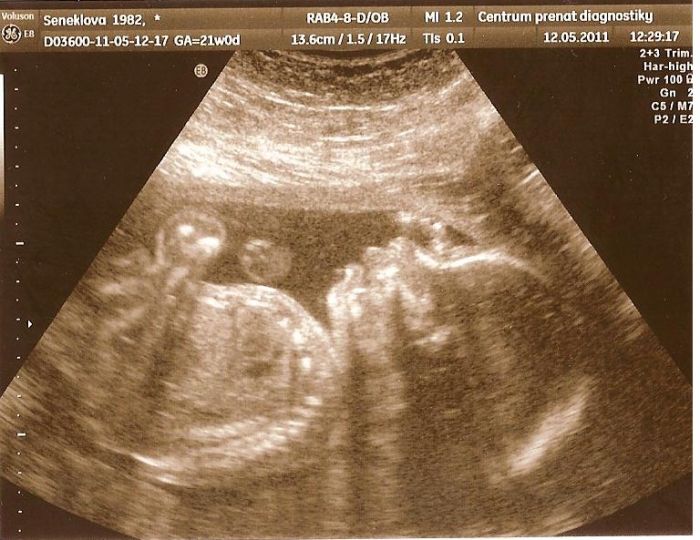

Marketto první odkaz mi pěkně sekl pc, škoda že jsem se napřed nepodívala dál. Ale mimušek nádhernej. Taky přidám ult. Holky ten můj malej má přední ret dopředu, napřed jsem se lekla jestli nebude mít nějaký předkus nebo něco ale pak jsem si vzpoměla že to doktorka pořizovala zrovna když polykal, tak snad to je jen takový záběr. kamarádka mě pak uklidnila že tak jsou všechny miminka ale Markett to tak na ult nemá. No ale budu se uklidňovat tím polykáním.